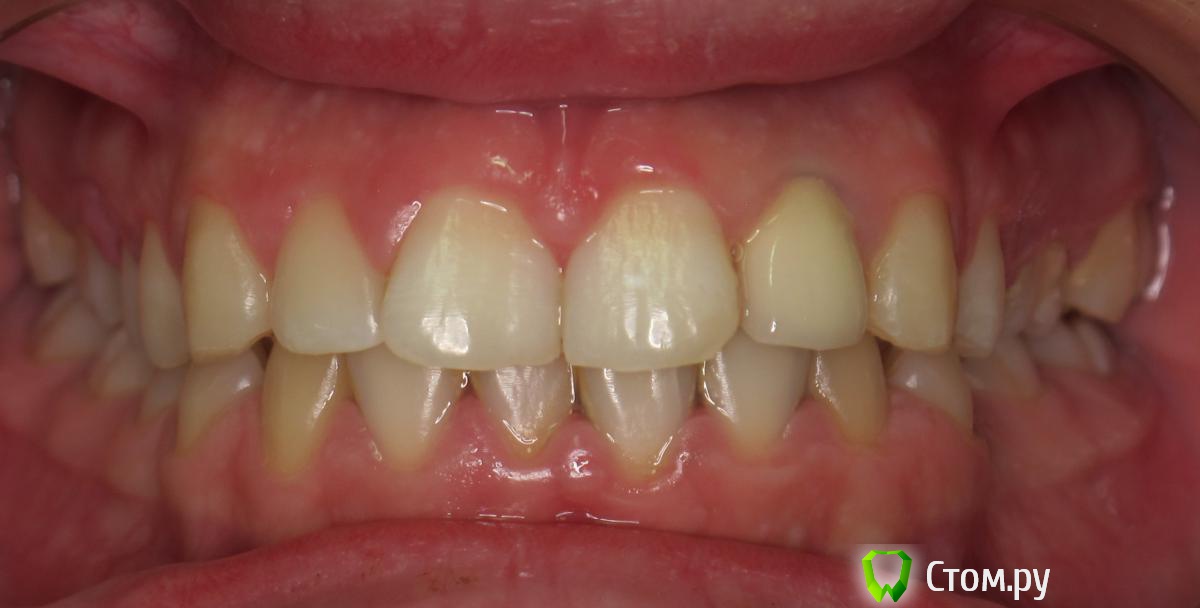

johniola Опубликовано 5 февраля, 2014 Поделиться Опубликовано 5 февраля, 2014 Девочка 19 лет из церковного приюта(иногда помогаю),22 зуб анкер+композит+хр периодонтитФото с свш +билд ап не нашёл,проостите Ссылка на комментарий

Bobby Опубликовано 6 февраля, 2014 Поделиться Опубликовано 6 февраля, 2014 Спасибо за публикацию. Видно что сделано, но не видно как. Все случаи индивидуальны и даже феррул-поддержка культевой части зуба будет иметь разные прогнозы у хрупкой молодой пациентки и мощного возрастного пациента. 2 Ссылка на комментарий